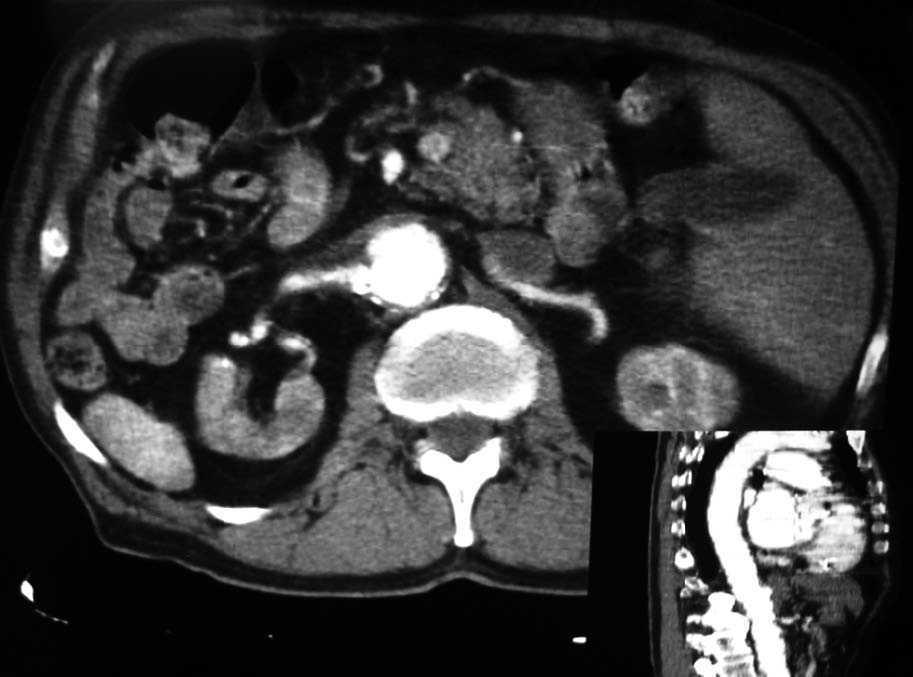

Las pruebas de imagen pueden establecer la fuente embolígena, lo cual es en ocasiones un verdadero reto, ya que muchos pacientes presentan ateromatosis diseminada. El ecocardiograma transtorácico puede ayudar a identificar las cavidades cardíacas como emisoras de émbolos. Se ha empleado el ecocardiograma transesofágico44, y se han observado la aterosclerosis moderada de la aorta torácica como engrosamiento de la íntima, con calcificaciones asociadas. La resonancia magnética y la angiotomografía abdominal con contraste suelen demostrar la presencia de trombos murales, placas de ateroma y aneurismas aórticos (fig. 3).

Figura 3. Angiotomografía toracoabdominal: imagen con contraste que muestra ateromas calcificados, e indentaciones en la aorta abdominal y en ambas arterias renales.